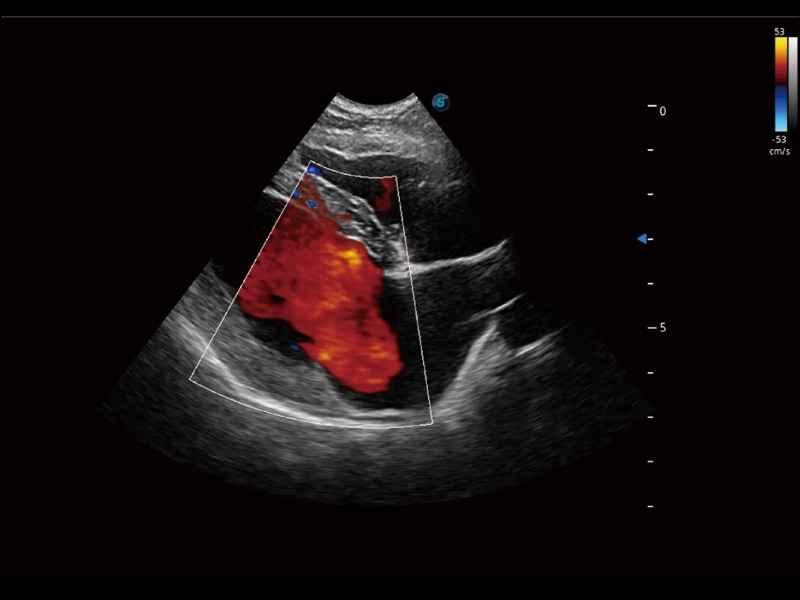

通过色彩血流和实时宽景相结合,可观察到完整的静脉或动脉的血流,方便医生检查。实时扫查过程中,如有任何操作失误也可以很容易地进行回扫擦除,而不会中断扫查。

通过创新的 Matrix E自适应滤波器和超长时间域算法,极大提升超低速微细血流的检出能力,同时更精准地滤除软组织和噪声信号,为兽用医生提供以往无法通过常规血流获得的疾病诊断信息。